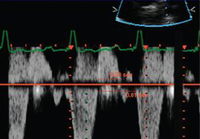

Doppler echocardiogram in a patient with pulmonary regurgitation following repair of tetralogy of Fallot, revealing a non-obstructed right ventricular outflow tract. The patient has a restrictive right ventricle

From: Chaturvedi RR, Redington AN. Heart. 2007 Jul;93(7):880-9; used with permission